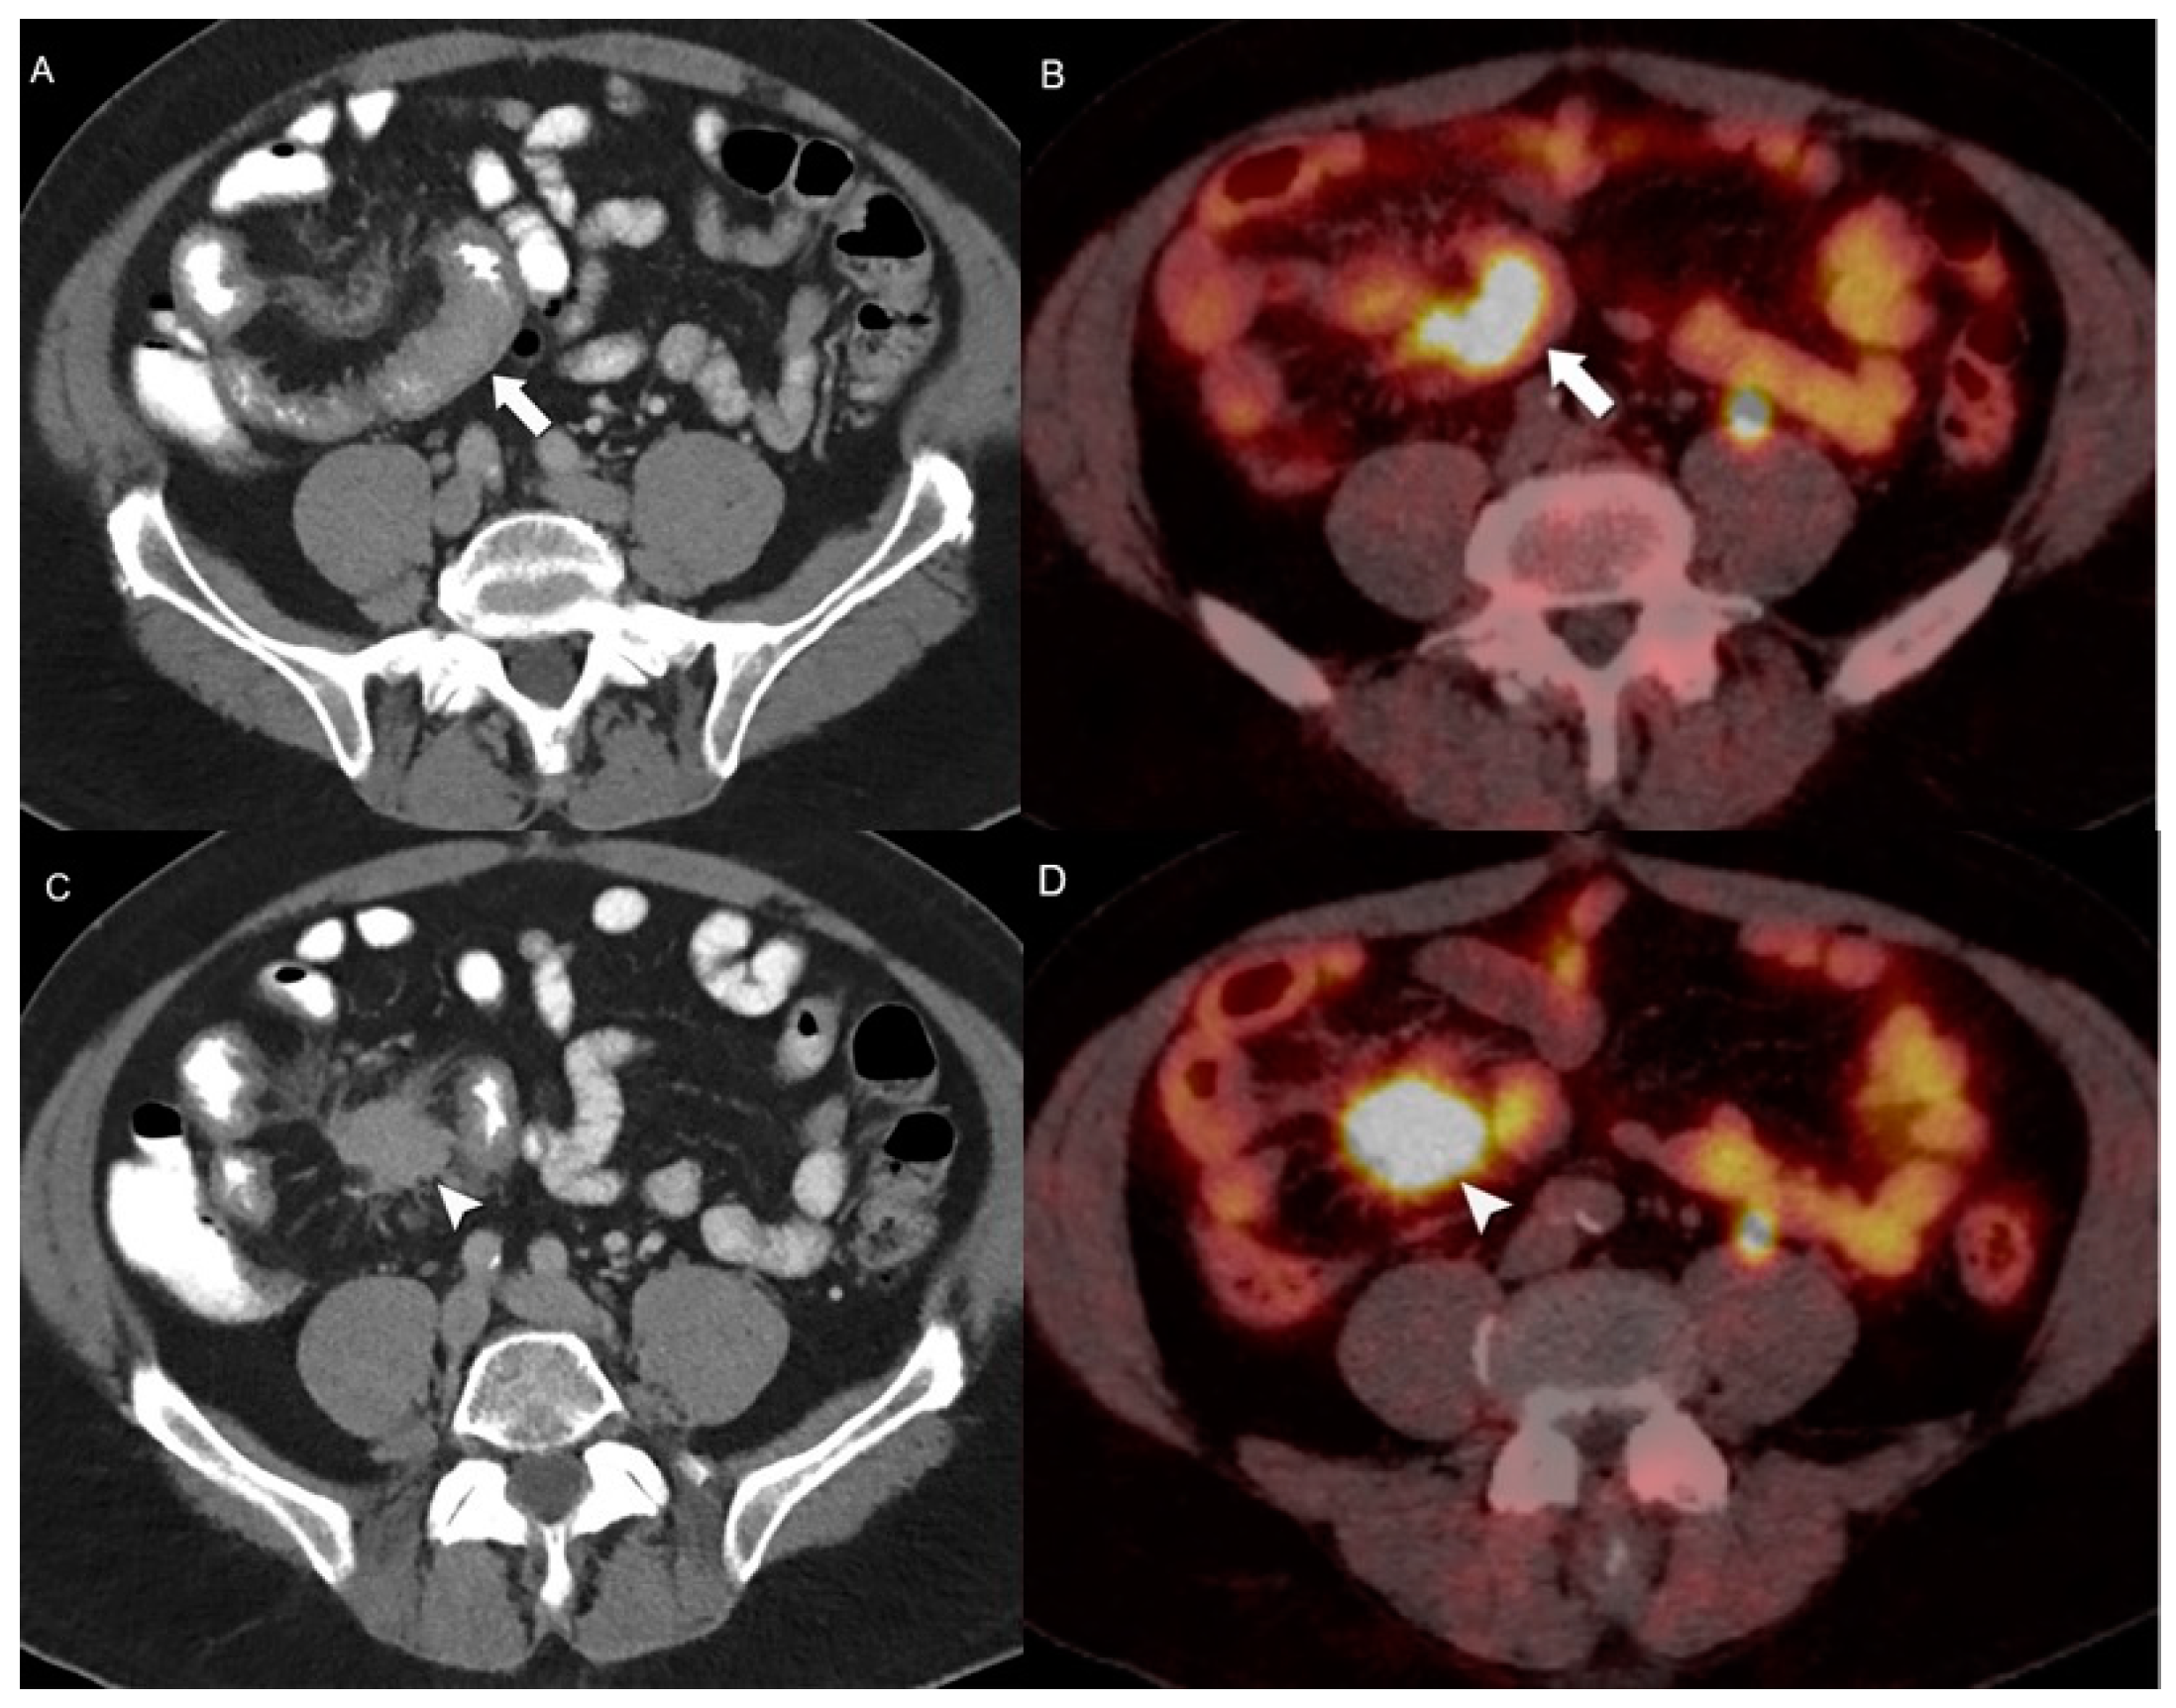

- Bozkurt, M.F.; Virgolini, I.; Balogova, S.; Beheshti, M.; Rubello, D.; Decristoforo, C.; Ambrosini, V.; Kjaer, A.; Delgado-Bolton, R.; Kunikowska, J.; et al. Guideline for PET/CT Imaging of Neuroendocrine Neoplasms with 68Ga-DOTA-Conjugated Somatostatin Receptor Targeting Peptides and 18F-DOPA. Eur. J. Nucl. Med. Mol. Imaging 2017, 44, 1588–1601. [Google Scholar] [CrossRef] [PubMed]

- Treglia, G.; Sadeghi, R.; Giovinazzo, F.; Galiandro, F.; Annunziata, S.; Muoio, B.; Kroiss, A.S. PET with Different Radiopharmaceuticals in Neuroendocrine Neoplasms: An Umbrella Review of Published Meta-Analyses. Cancers 2021, 13, 5172. [Google Scholar] [CrossRef] [PubMed]

- Ambrosini, V.; Kunikowska, J.; Baudin, E.; Bodei, L.; Bouvier, C.; Capdevila, J.; Cremonesi, M.; de Herder, W.W.; Dromain, C.; Falconi, M.; et al. Consensus on Molecular Imaging and Theranostics in Neuroendocrine Neoplasms. Eur. J. Cancer 2021, 146, 56–73. [Google Scholar] [CrossRef]

- Karfis, I.; Marin, G.; Levillain, H.; Drisis, S.; Muteganya, R.; Critchi, G.; Taraji-Schiltz, L.; Guix, C.A.; Shaza, L.; Elbachiri, M.; et al. Prognostic Value of a Three-Scale Grading System Based on Combining Molecular Imaging with 68Ga-DOTATATE and 18F-FDG PET/CT in Patients with Metastatic Gastroenteropancreatic Neuroendocrine Neoplasias. Oncotarget 2020, 11, 589–599. [Google Scholar] [CrossRef] [PubMed]